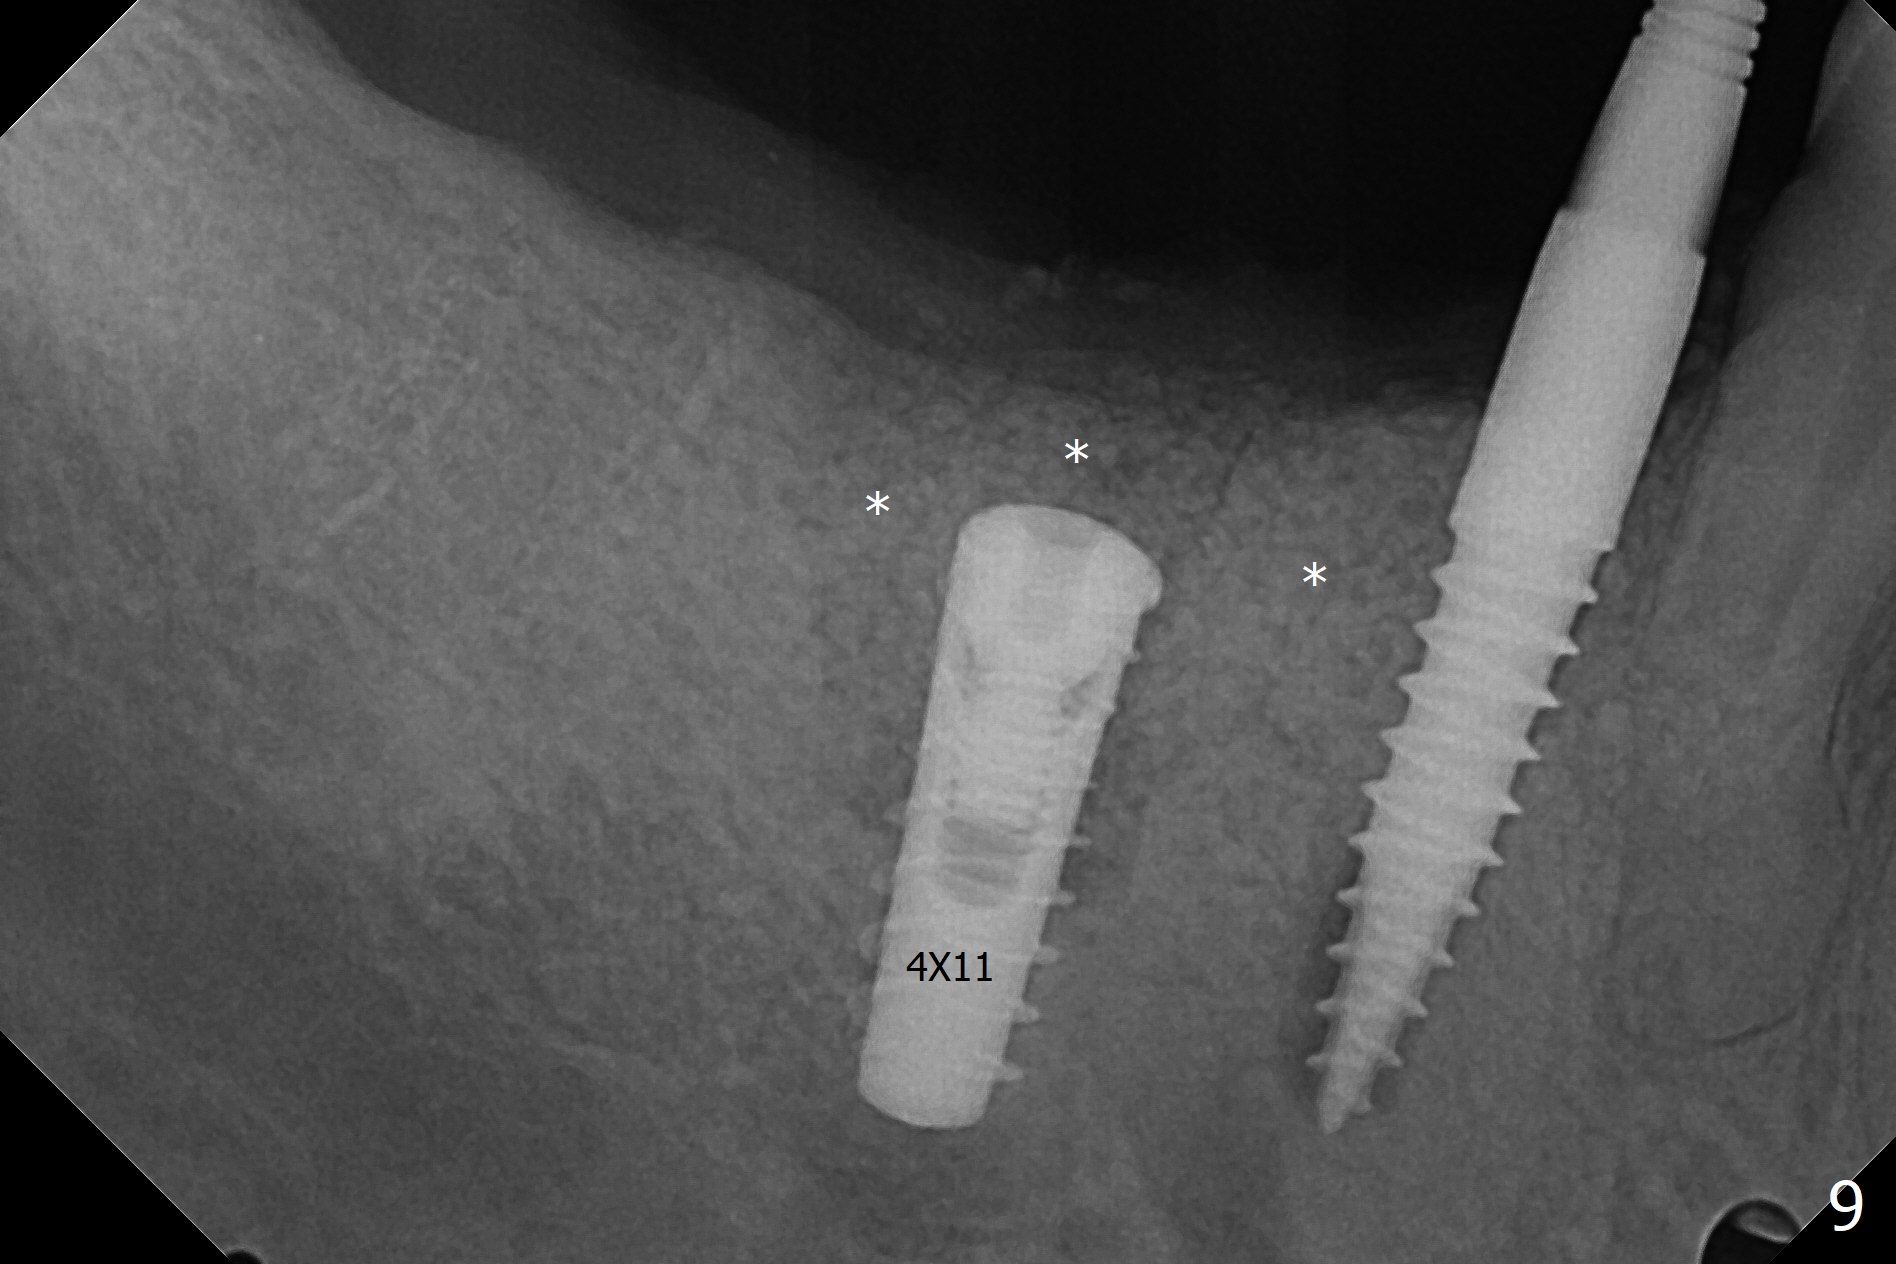

The buccal gingiva is recessive at #29 and 30 (Fig.1). Incision reveals buccal implant thread exposure with circum-ferential granulation tissue (Fig.2 *). Immediate post implant removal at #29, osteotomy is initiated lingual (Fig.3 (intraop CT, coronal section) ). A smaller and shorter implant (3x12 mm vs. 3.5x13 mm) is placed away from buccal (Fig.4 B, 5).

The implant at #30 was also buccally placed (Fig.6,7) and should be corrected in the same manner (Fig.7 green). Due to the bone being harder in the molar region, a smaller and shorter implant (4x11 mm vs. 5x13 mm) shifts slightly buccally while being placed (Fig.8,9). Since primary stability is lower (<20 Ncm vs. 35 Ncm associated with the implant #29), an abutment is not placed, which may be favorable to healing, but it is difficult to achieve primary closure. After bone graft (Fig.9 *) and 2 layers of PRF, Cytoplast is placed. Cytoplast appears to be exposed buccally (Fig.10 <) and occlusally (Fig.11 ^) asymptomatic 9 days postop. Exposure of Cytoplast is more distinct without sign of infection 15 days postop (Fig.12). The patient returns with chief complaint of "foul smell" 7 weeks postop (coronavirus lockdown). Although the Cytoplast exposes more (Fig.13 (* exposed; @ unexposed)), the underlying gingiva remains healthy (Fig.14). While the bone height decreases at #29, the bone density at #30 increases 4.5 months postop (Fig.15). The gingiva heals. The implant at #30 is uncovered 6 months postop. The lingual plate has to be removed for the uncover, while the coronal end of the buccal one is missing. No bone graft is added. When the 4.5x4 mm healing abutment is removed 6.5 months postop, the buccal plate looks concave at #30 (Fig.16' *). The buccal plate looks thin at #29 with a cotton roll placed buccally (Fig.16 R). The lingual plate at #29 is coronal to the buccal one (Fig.17). The buccal gingiva at #29 is quite long (Fig.18). The coronal buccal plate appears to be missing (Fig.19 >), which will be watched. A 4.5x7.5(4) mm cemented abutment is torqued (Fig.20).